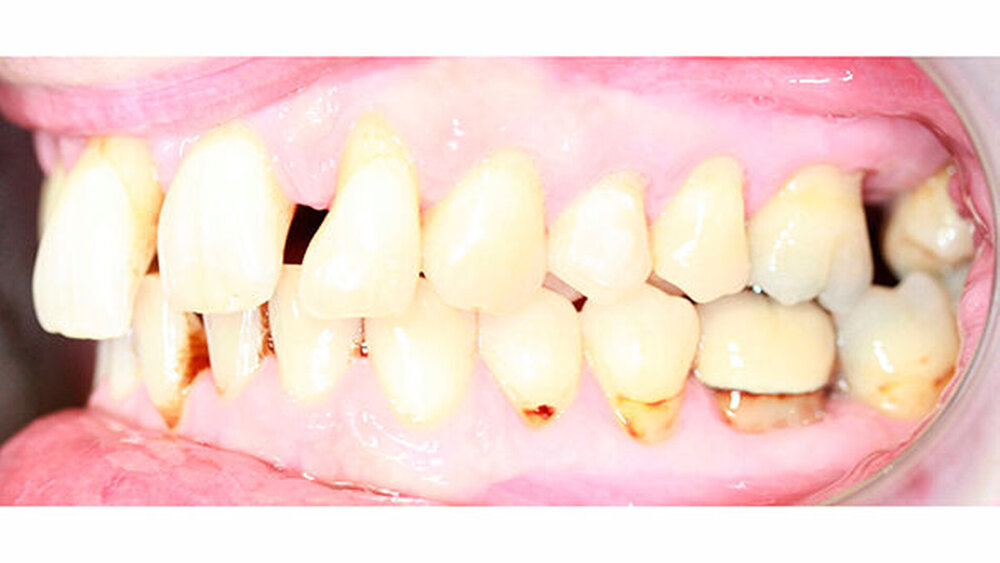

Nach erfolgter Parodontitistherapie und konservierender Versorgung stellte sich der Patient Ende 2014 erneut in unserer Praxis vor.

Die Sulkustiefen konnten auf etwas weniger als 4 mm reduziert werden, während der Blutungs- und Plaque-Index bei weniger als 15 Prozent lag. Daher wurde eine kieferorthopädische Behandlung über die nächsten zwei Jahre in Kombination mit engen zahnärztlichen Kontrollen geplant. Als Mittel der Wahl entschieden wir uns gemeinsam mit dem Patienten für das Invisalign-System, da hiermit sowohl eine Schienung als auch eine kraft-arme Bewegung der Zähne möglich sein sollte. Für den Frontzahnbereich wurden keine Attachments geplant, so dass hier eine unnötige Hebelwirkung umgangen werden konnte (Abbildung 3).

Um einen kompletten Lückenschluss im Oberkiefer zu ermöglichen, musste im Unterkieferfrontzahnbereich zusätzlich zur Derotation und Positionierung der Zähne - insbesondere Zahn 41 - von approximaler Schmelzreduktion, kurz ASR , Gebrauch gemacht werden, um einer Tonn`schen Diskrepanz entgegenzuwirken (Abbildung 4).